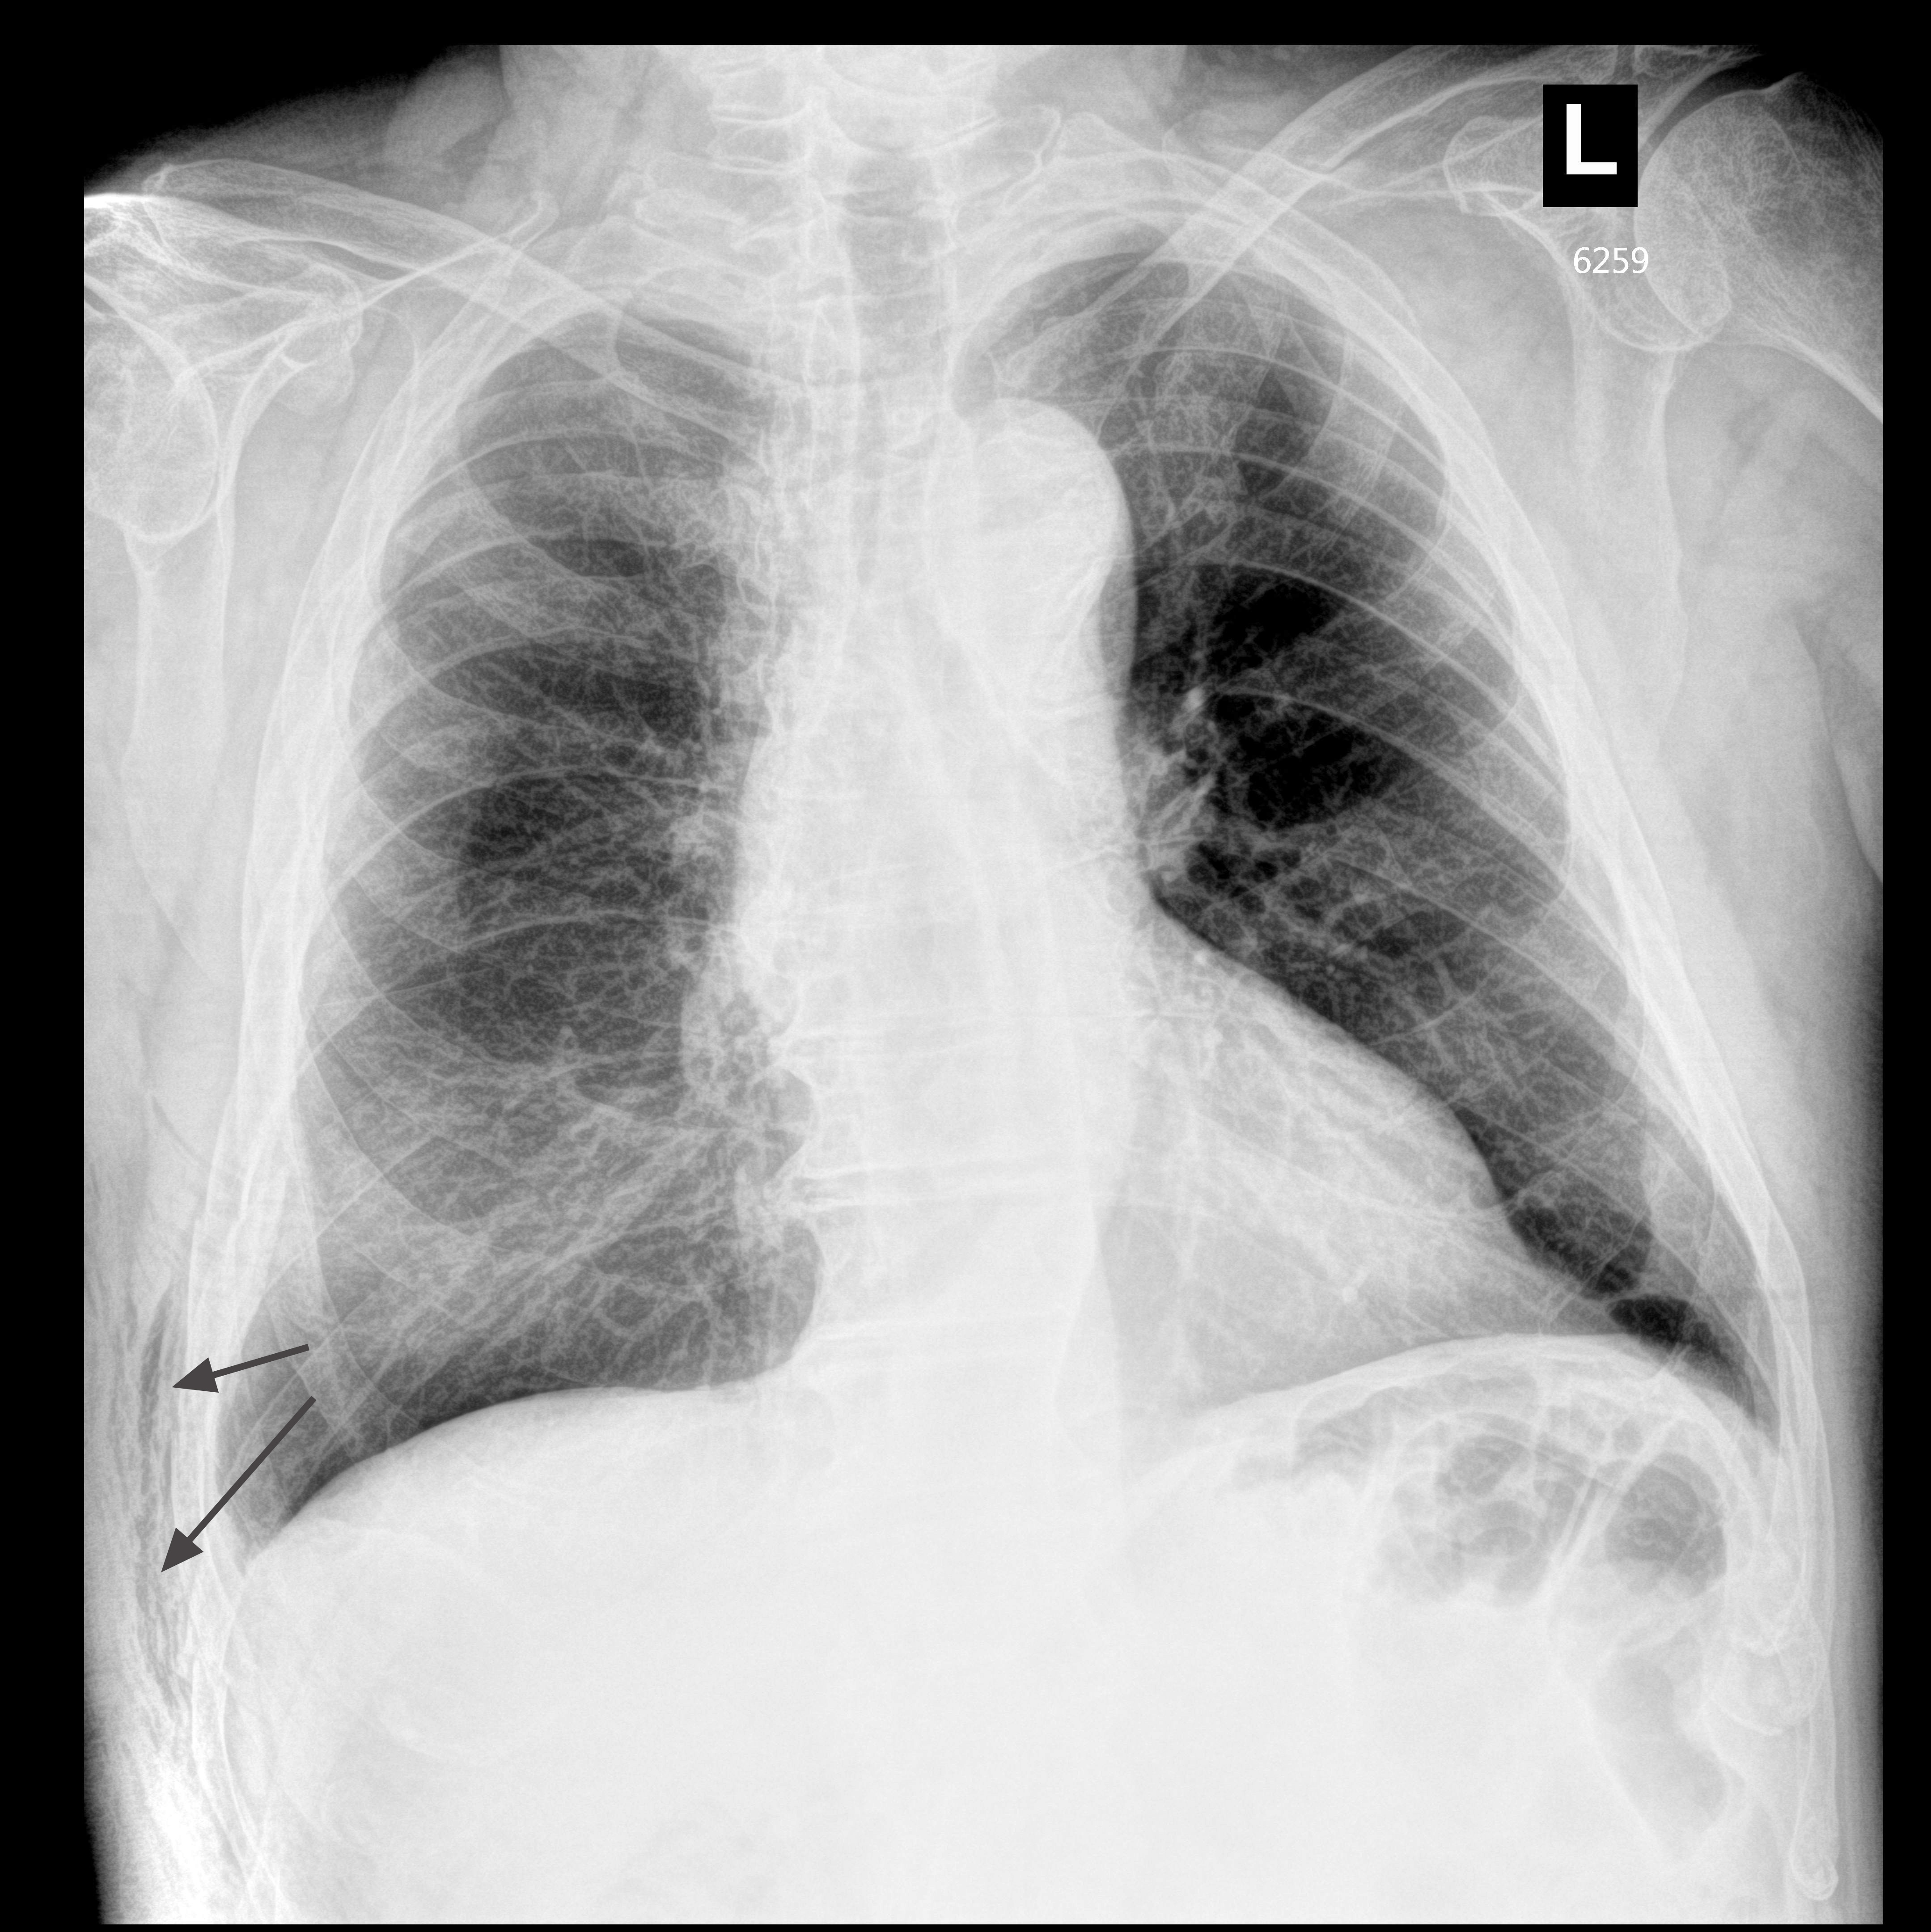

aerarrows.jpg

На рентгенограмме определяется воздух в мягких тканях, данных за массивный пневматоракс нет.

Таким образом, УЗИ является довольно чувствительным и информативным методом в диагностике пневматоракса при травме грудной клетки.